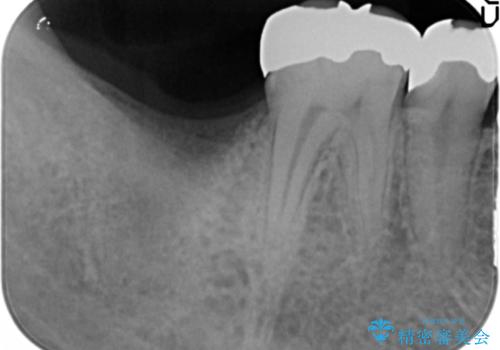

レントゲン及びCTを撮影し骨の状態を確認したのち、アルファタイトインプラントによる治療を行いました。